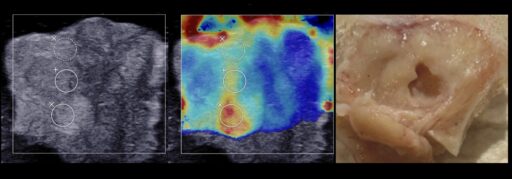

Также недавно мы впервые экспериментально показали возможность получения локализованных механических разрушений в ткани злокачественной опухоли предстательной железы человека ex vivo.

На данный момент в Лаборатории ведутся исследования на большей выборке препаратов для изучения отклика различных опухолей предстательной железы на механическое разрушение методом гистотрипсии с кипением, влияния их упругих свойств на этот отклик, а также для определения диапазона оптимальных параметров воздействия для эффективного и быстрого разрушения различных новообразований предстательной железы.